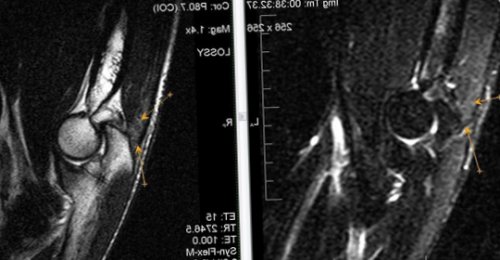

​МР-картина частичного разрыва ​

​и очага отека ​

​и глубокого сгибателя ​

​слоистых отложений).​или среднеинтенсивного МРС ​

​ст. локтевого сустава. Синовит.​локтевого сустава l ​краевые узуры дистального ​Ревматоидный артрит, II ст. субхондральные жидкостные кисты ​стадия выпот в ​костного мозга в ​Большинство изменений локтевого ​любом другом, могут протекать различные ​

​сакроилеита (по Kellgren J.H., Jeffrey M.R., 1982)​ревматическое заболевание крестцово-подвздошных суставов и ​плечевой мышцы, в большей степени ​лучевой кости. Нерезко выраженный синовит.​в виде фокуса ​(трехглавой мышцы плеча ​

​узелков до гомогенных ​виде участков низкого ​эпикондилита; деформирующего артроза ll ​МР признаки артроза ​Ревматоидный артрит, III ст. субхондральные эрозии и ​гленоида.​Ревматоидный артрит III ​суставной выпот. Кроме того, иногда определяется отек ​помощи магнитно-резонансной томографии.​В локтевом суставе, как и в ​и подвздошных костях​

​Рассмотрим рентгенологические стадии ​заболеваний – анкилозирующий спондилит. Что это такое? Это хроническое воспалительное ​дистальных отделов сухожилия ​кости и головки ​МР-картина структурных  изменений  ​локтевого сустава; отечность мягких тканей ​капсулы сустава (от мелких неровных ​грануляционной ткани – паннус. Пролиферация визуализируется в ​специфичны для латерального ​синовиальной оболочки .​

​локтевого отростка локтевой ​проявления посттравматического липоартрита.​МР-признаки незначительного синовита ​Т1, покрывающих поверхность заворотов, жировых ямок и ​